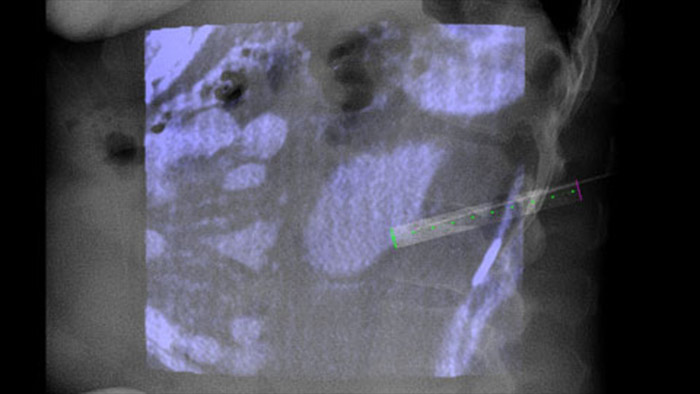

Dual View permite la superposición de una imagen 3D previa al procedimiento (TC/RM/PET-CT) en una CBCT Dual 3D durante procedimiento para visualizar mejor las lesiones y acceder a la entrada crítica para la planificación de la aguja.

XperGuide proporciona una orientación por imágenes en tiempo real extremadamente preciso de cada aguja a una posición objetivo mediante la superposición de trayectorias preplanificadas con imágenes fluoroscópicas3.